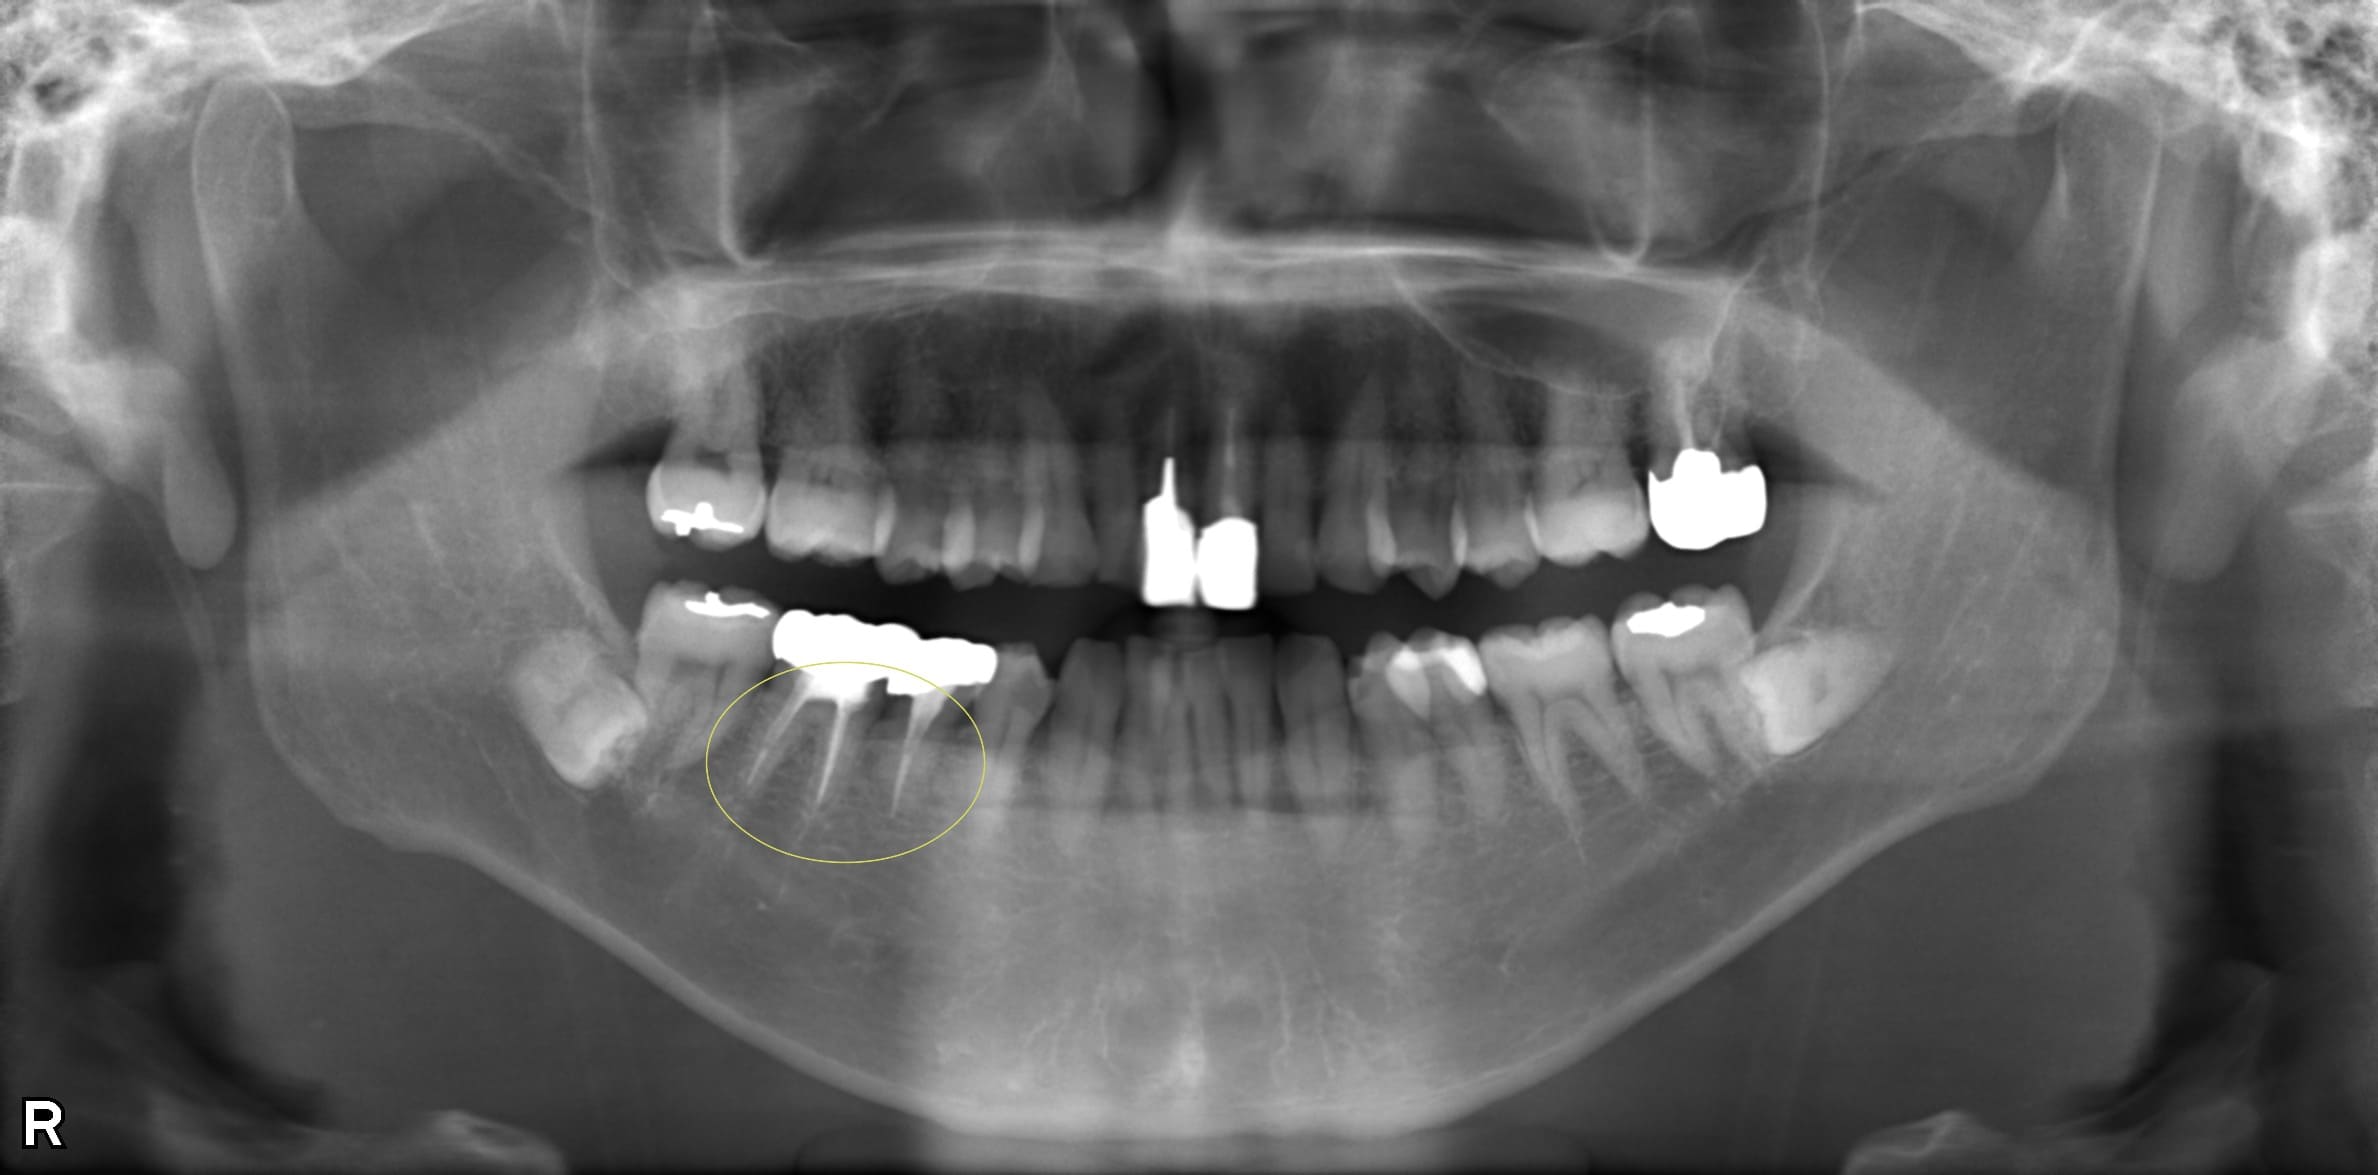

| 歯科用CTによる三次元診断 | 拡大ルーペの使用 |

| 一般的なレントゲン(二次元)では見えない、歯根の複雑な構造や病巣の位置を立体的に正確に把握し、治療の見落としを防ぎます。 | 肉眼では困難な根管内の細部を約8倍に拡大して確認し、処置の精度を高めます。 |

| 歯科用CTによる三次元診断 |

| 一般的なレントゲン(二次元)では見えない、歯根の複雑な構造や病巣の位置を立体的に正確に把握し、治療の見落としを防ぎます。 |